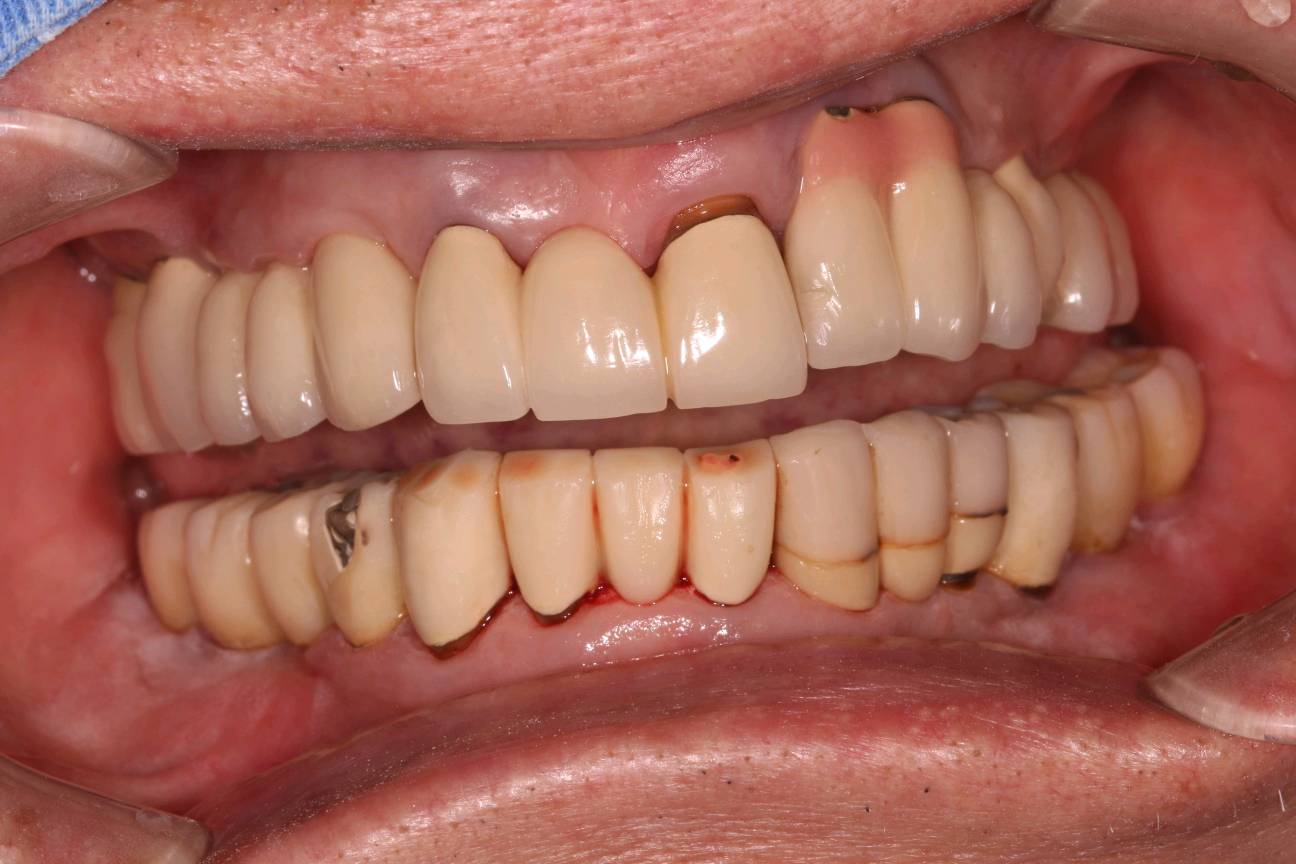

程先生,80岁种植牙复诊,共种了17颗牙,距离第一颗种植牙己定期随访15年,无松动疼痛等症状,用的很是满意。

本次复诊进行了OHI口腔卫生宣教,刷牙、牙线、间隙刷使用宣教和全口超声波洁治,喷砂洁治,抛光,上药,并愉快的约了明年今日复诊。